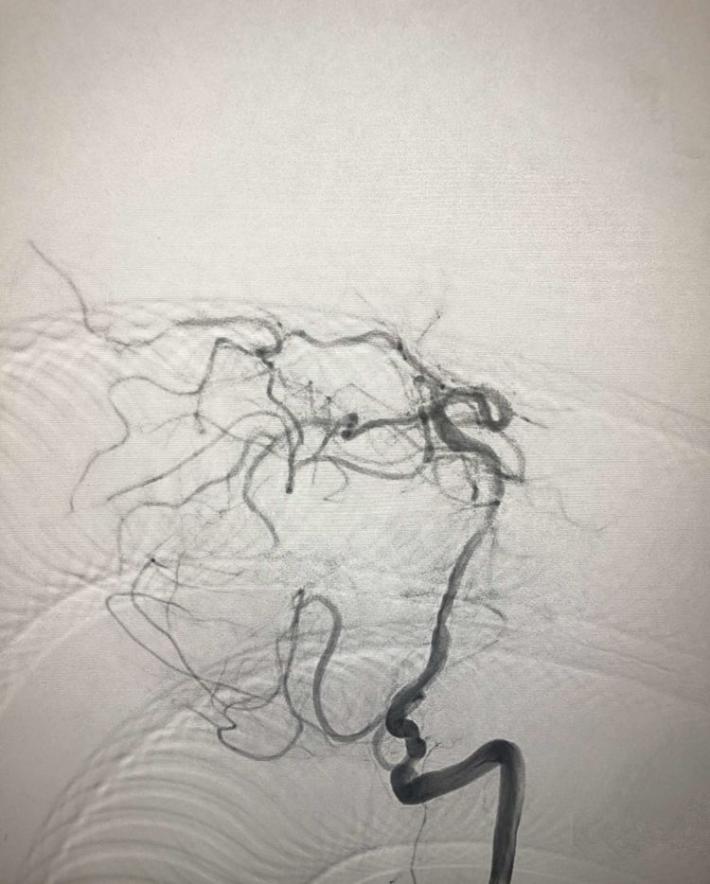

入院后75min,股动脉穿刺成功,后循环造影及右侧颈内动脉正侧位。

导丝导管通过闭塞部位,经微导管造影,证实在远端真腔内,取栓后M1重度狭窄,球囊扩张。

球囊扩张

支架植入术后前向血流通畅